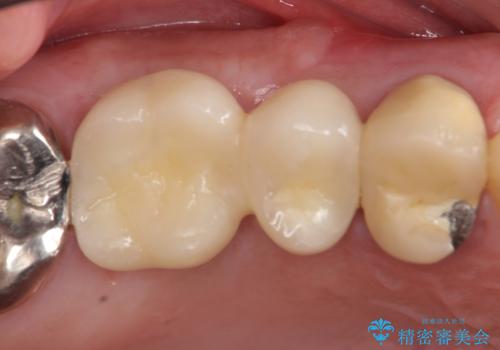

右上の567ブリッジを外したところ、右上5は歯根破折により保存不可能だったため、右上56部にインプラントを埋入し欠損補綴を行いました。

今回用いたオールセラミッククラウンはジルコニアフレームという白い素材の上にセラミックを盛っているため、審美性が非常に高いのが特徴です。

また、ジルコニアは人工ダイヤモンドの材料にも使われているほど高い強度を持っており、そのためオールセラミッククラウンは審美性だけでなく、奥歯やブリッジの補綴も可能とするクラウンです。